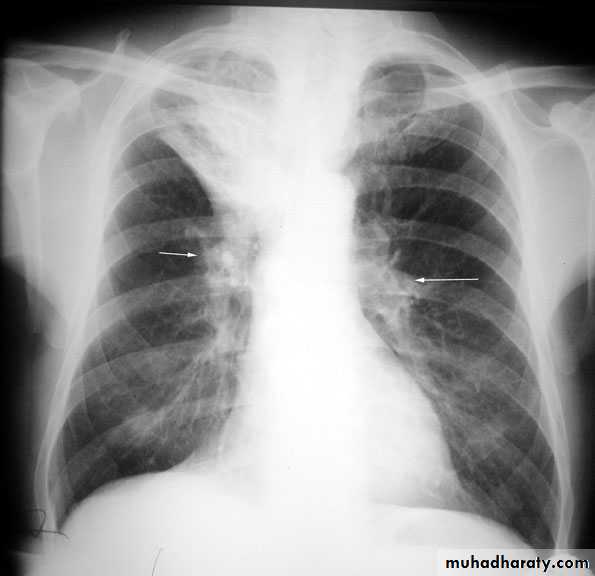

Upper lobe c. Middle lobe c.

rt lower lobe c. Left lower lobe c.